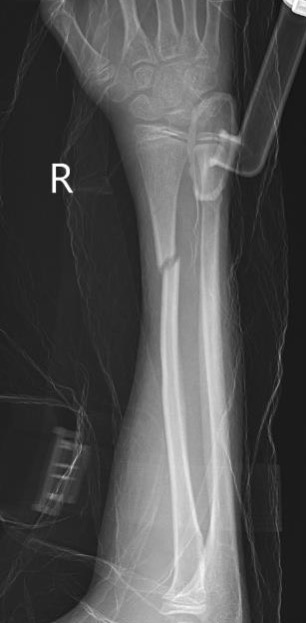

Complete

Greenstick

Buckle / torus

Single or both bone

Non Operative Management

Acceptable Position

< 10 years old: < 15 degrees malalignment

> 10 years old: < 10 degrees malalignment

< 1 - 2 years of growth remaining: Anatomic alignment required

Operative Management

Indications

Outside parameters for non-operative treatment (see above)

Loss of reduction

Options for displaced fractures

1. MUA

- young patients < 10

- greenstick fractures